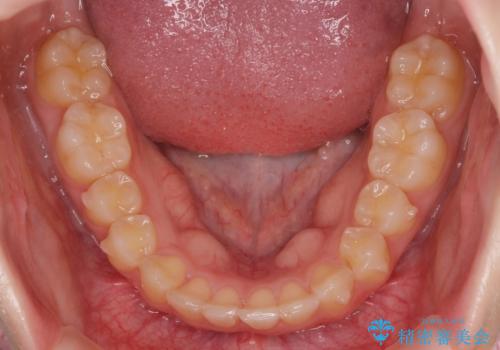

- 突出感のある、前歯の矯正治療を求めて来院されました。

軽度な突出・ガタつきを26枚・約半年の矯正治療期間で計画するインビザラインモデレートプランで治療を始めて行きます。

約半年といった短期間で、前歯の角度やガタつきを改善することができました。